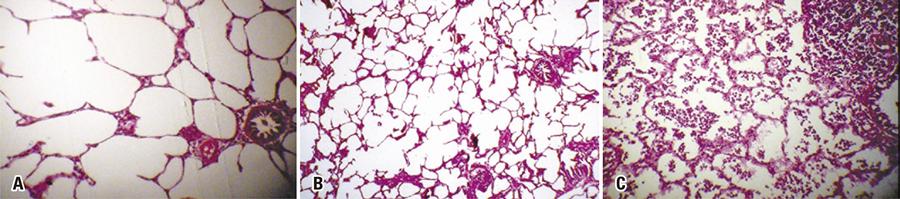

Foram obtidas 30 amostras em 10 órgãos diferentes, divididos em três intervalos de tempo distintos. Quando o sistema foi acionado por 5 segundos, gastaram-se 14g de gás; por 10 segundos, 27g; e por 15 segundos, 40g; o gasto médio foi de 2,7g/s pelo cateter de 1,8mm. O sistema confeccionado com tubo de gás e cateter proporcionou resultado efetivo, com dispersão adequada e constante do gás, congelamento adequado e de fácil execução. Apesar da técnica evidenciar congelamento efetivo, na microscopia não houve alteração tecidual. Isso ocorreu porque o pico de lesão tecidual por congelamento ocorre após 48 horas, o que não foi possível avaliar por este método proposto.